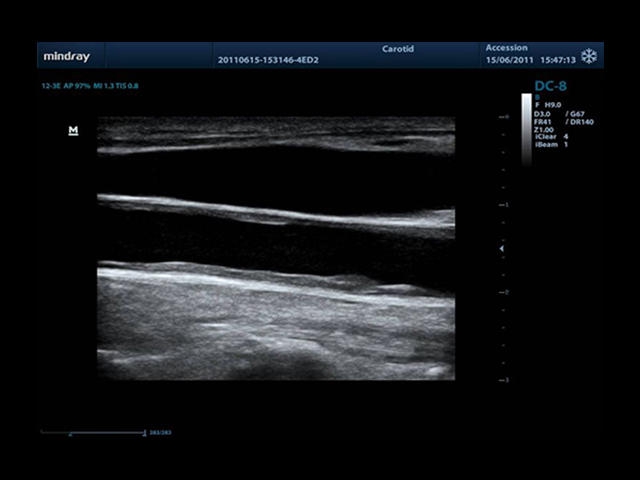

• Auto IMT Package - измерения и анализ толщины комплекса интима-медиа (КИМ) сонной артерии.